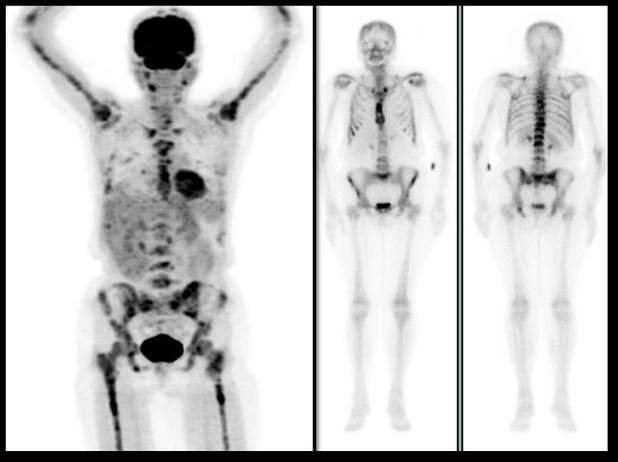

Figura 3.

Figura 3. Paciente de 63 años con diagnóstico reciente de cáncer de mama, con patología articular inflamatoria de larga evolución. El gammagrama óseo (imágenes de la derecha) pone de manifiesto los cambios inflamatorios en grandes articulaciones, pero no hace evidentes lesiones en pelvis vistas en el PET (izquierda). En escápula izquierda se aprecia claramente una lesión que puede confundirse con etiología inflamatoria de hombro.